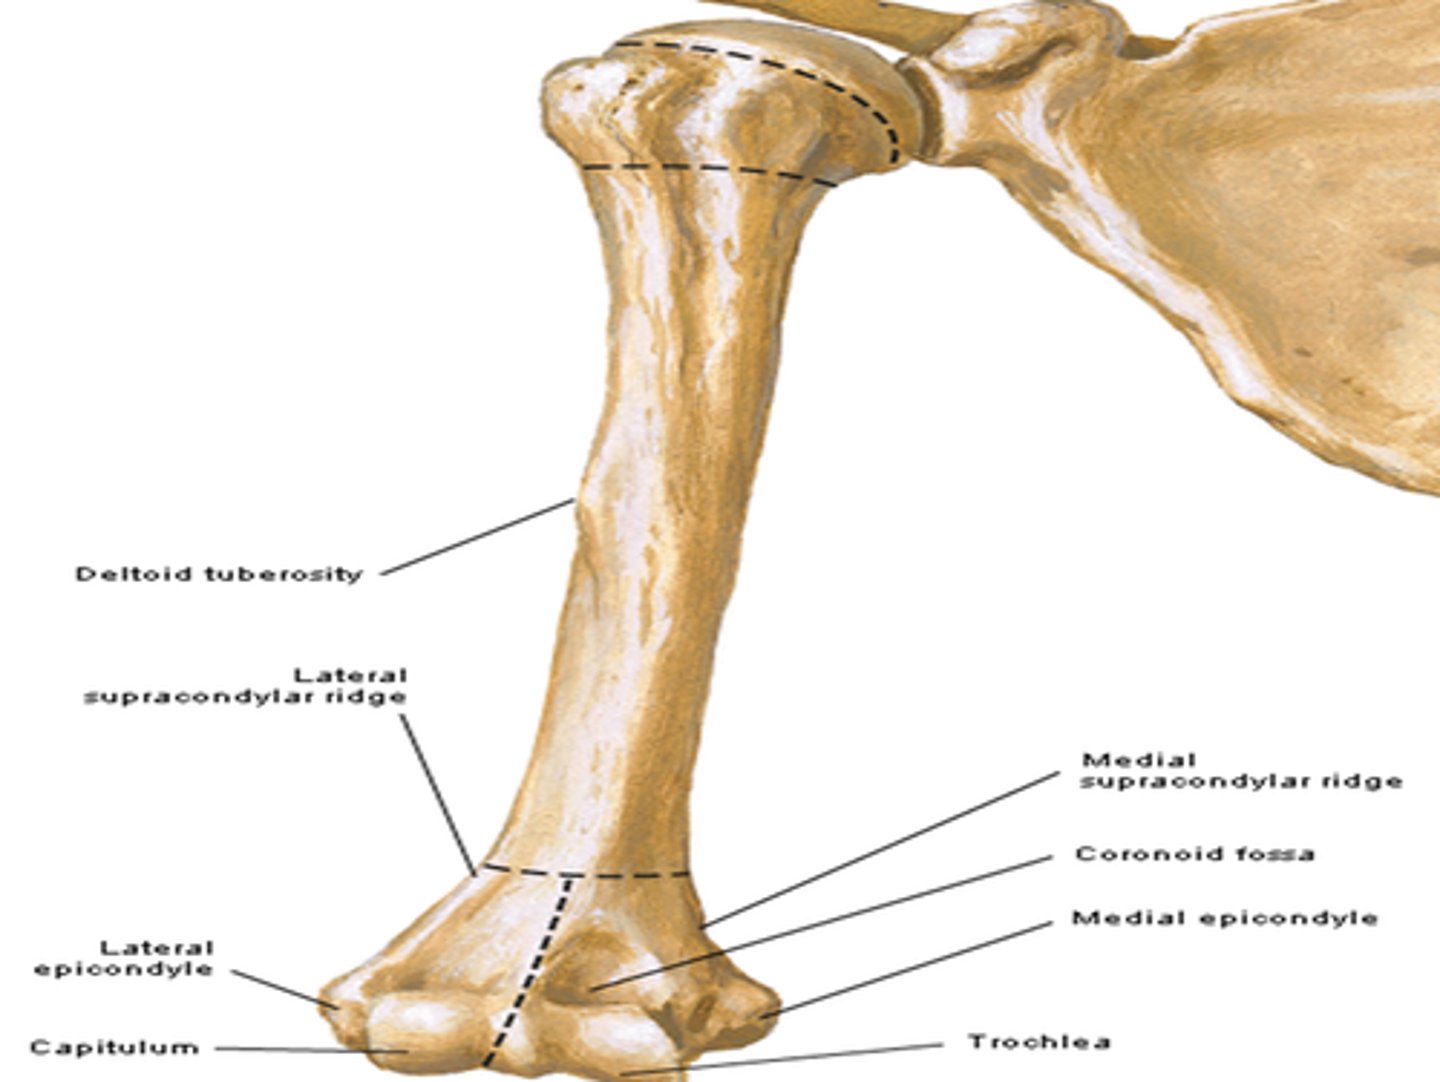

The humerus is the ______ bone in the UE

largest

What bones do the humerus articulate with?

- scapula via glenohumeral joint

- radius & ulna via elbow joint

Features of the humerus:

- head

- anatomical nech

- surgical neck

- greater tubercle

- lesser tubercle

- intertubercular groove

- shaft

- deltoid tuberosity

- radial groove

- medial and lateral supra-epicondylar ridges

- condyle

- capitulum

- trochlea

- coronoid fossa

- olecranon fossa

Head of the humerus:

articulates with glenoid cavity of scapula

Anatomical neck of the humerus & its function:

- groove

- separates the head from the greater and lesser tubercles

- indicates the place of attachment of the glenohumeral joing capsule

Surgical neck of humerus:

- narrow part distal to head and tubercles

- common site of fracture!!!

Greater tubercle of humerus:

lateral position from head

Lesser tubercle of humerus:

anterior position from the head

Intertubercular groove of humerus:

- located between tubercles

- provides passage for the tendon of the long head of the biceps muscle

Clinical relevance of humerus:

axillary nerve wraps around the surgical neck. fracture of the surgical neck may damage the axillary nerve. Integrity of this nerve is tested by touching the deltoid, since the nerve provides sensory innervation to this area of the shoulder region

Shaft of the humerus:

long portion of the humerus with a tuberosity and a groove, engrossing distally

Deltoid tuberosity of humerus:

attachment for deltoid muscle

Radial groove of the humerus:

oblique demarcation on posterior side. Contains the radial nerve and deep artery of arm (named after the nerve)

Medial and lateral supra-epicondylar ridges of the humerus:

End distally as the medial and lateral epicondyles, involved in muscle attachment